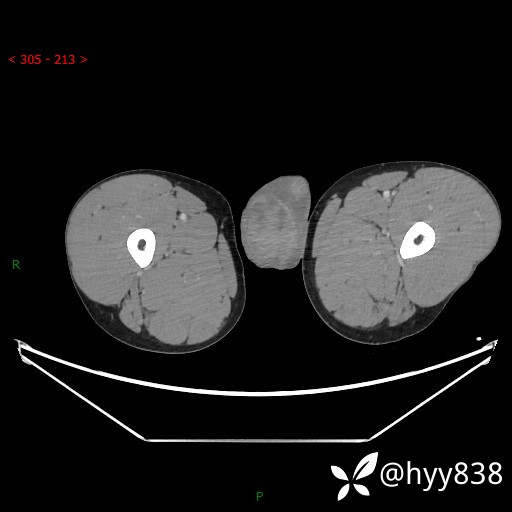

讨论:病变性质?

静脉期